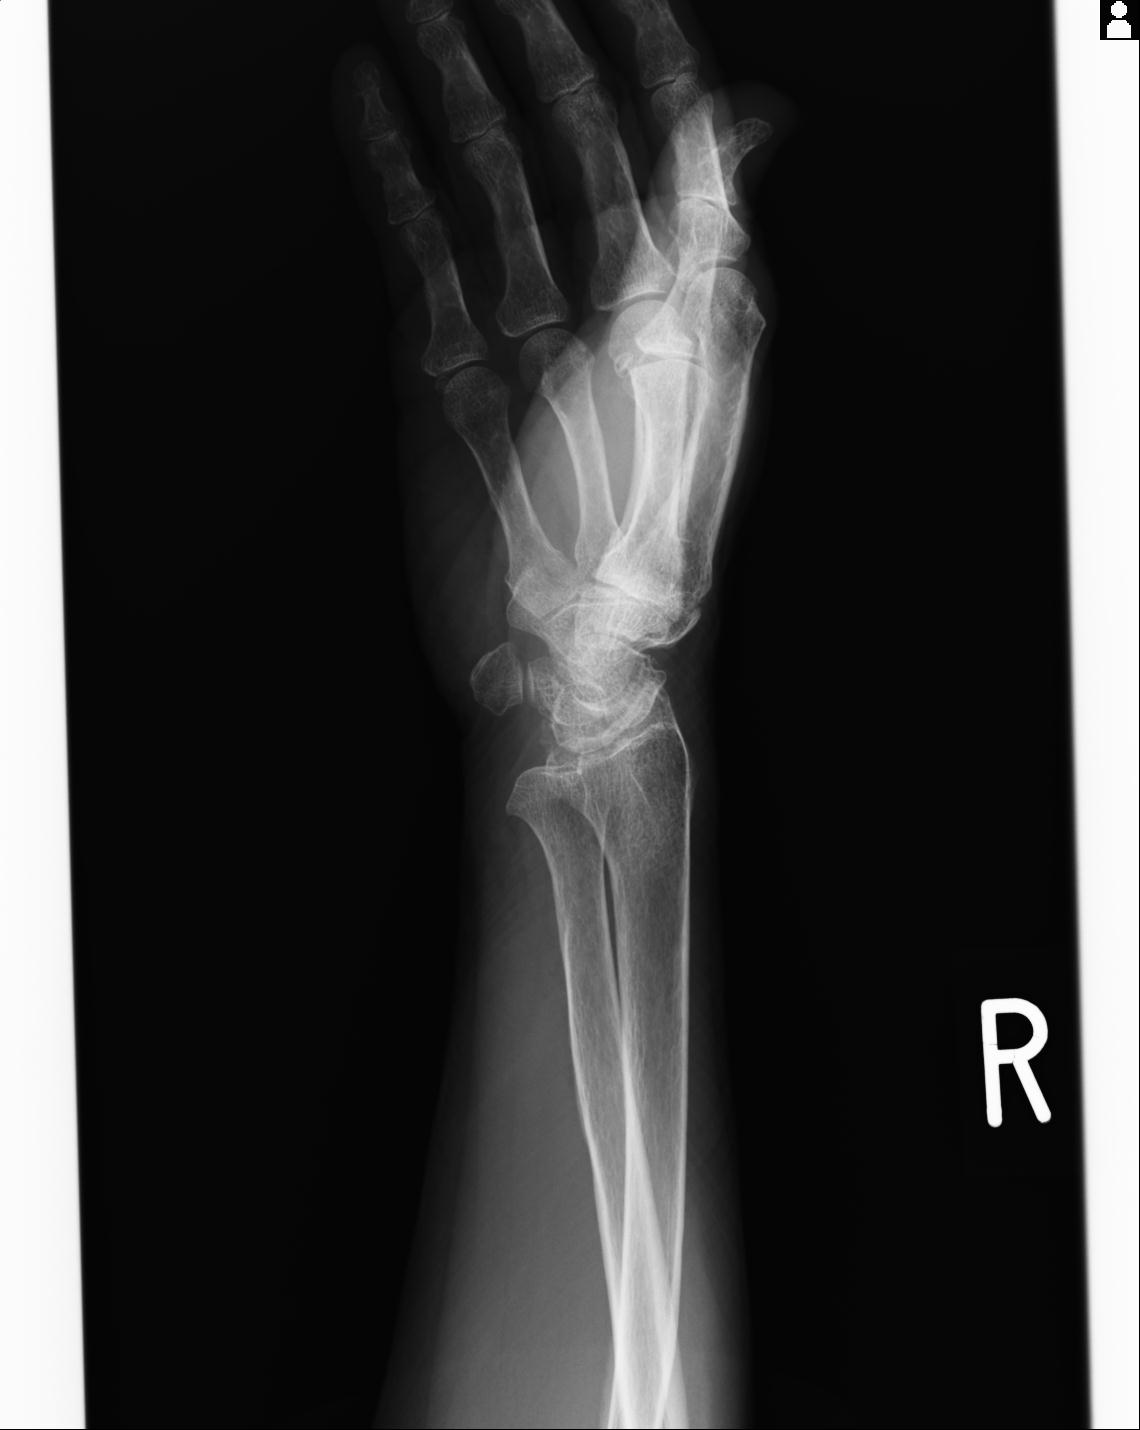

46666 1/23 両股正面+軸と右手関節 2R 76歳女性 右橈骨遠位端

46666 1/28 両股正面+軸と 1/26 右手関節 2R 76歳女性 右転子部骨折

50435 1/4 1/15 手関節 4R 17歳女性 右橈骨遠位端

102739 12/30 1/5 左手関節 4R 92歳女性 橈骨遠位端

101290 1/4 5/21 5/20 手関節 2R 17歳男性 橈骨遠位端